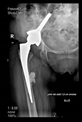

The direction of the cup stem was determined by the guide wire. The aiming device was needed to introduce this wire. After removing the aiming device, the next step was the drilling. Since a cannulated drill bit was used, the previously installed wire could guide the process. A self-positioning reaming tool was then used in the drilled channel. In the prepared cavity, the cup was fitted perfectly. Of the two stemmed cups available to us, the McMinn cup (Waldemar Link, Hamburg, Germany) had the simpler geometry and was therefore chosen. The stemmed cup was inserted according to the manufacturer’s recommendation. In the presence of a significant bone defect, a synthetic bone graft may be impacted for substitution.

The radiological examination allowed us to verify the close bone-to-implant contact and the unchanged position of the implant during follow-up.

In all the cases operated with the above-described targeting procedure, the stems of the cups remained between the cortical bone surfaces without perforation of the linea terminalis, as shown by postoperative radiographs. There were no complicated surgical situations. In 16 cases, the wound healings were uneventful, and the hips were able to bear weight again after postoperative rehabilitation.